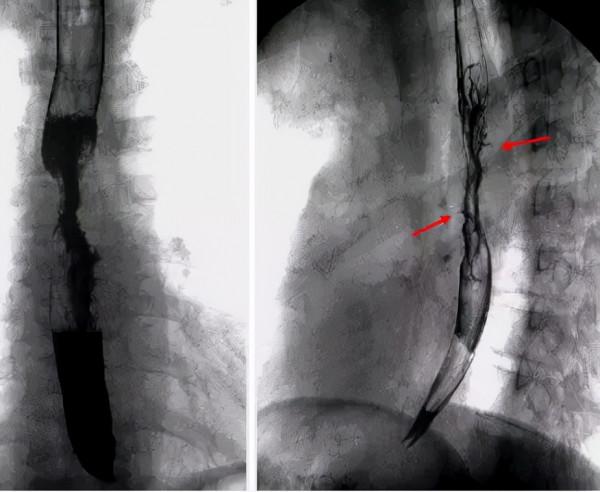

食管鋇餐造影顯示:食管邊緣毛刺狀、龕影、食管黏膜僵硬、鋇劑中斷

食管鋇餐顯示:食管壁光滑、龕影消失;